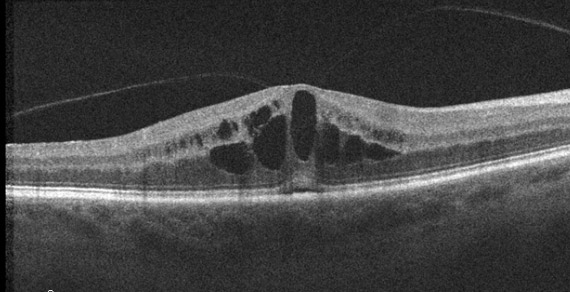

This patient lost their vision after an MVA. Why?

In this image there is evidence of vitreomacular adhesion. In the center of the image, there is intraretinal fluid in the inner nuclear layer and at the junction between the outer plexiform/nuclear layer. There is also some subretinal fluid. The patient’s angiogram demonstrates a petaloid pattern (video). The ellipsoid is a little thickened centrally.

This patient was diagnosed with whiplash maculopathy.